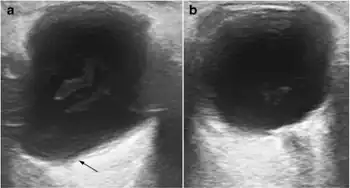

| a) Shows the lengthened anteroposterior axis of right eye, with a pear-shaped posterior pole sacculation known as a staphyloma b) compare with the normal left globe | |